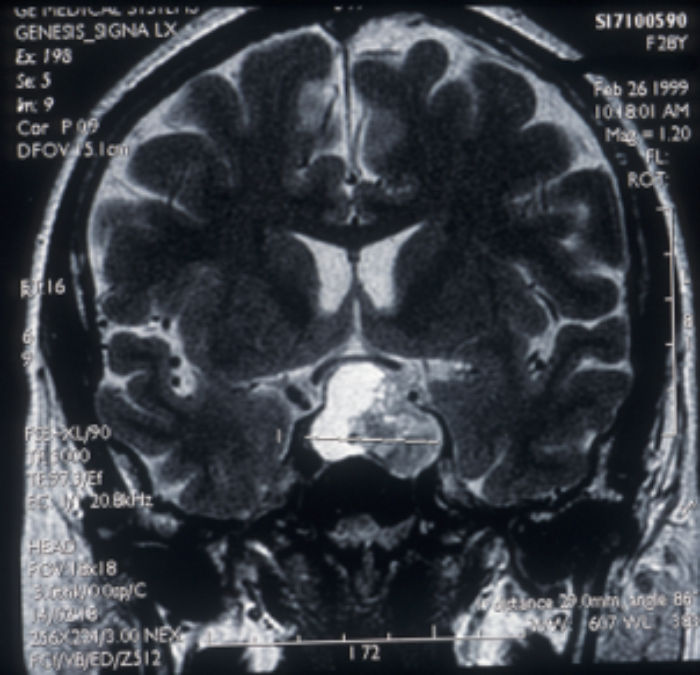

Figure 6: MRI scan coronal image showing haemorrhage into a pituitary tumour.

Pituitary apoplexy is correctly defined as acute haemorrhagic necrosis of a pituitary adenoma leading to rapid tumour expansion accompanied by headache, lethargy, coma and increased intracranial pressure (Figure 5). Development of a cranial nerve palsy associated with tumour expansion is not apoplexy nor is a localised haemorrhage into a tumour (Figure 6) although these may result in an acute exacerbation of symptoms.